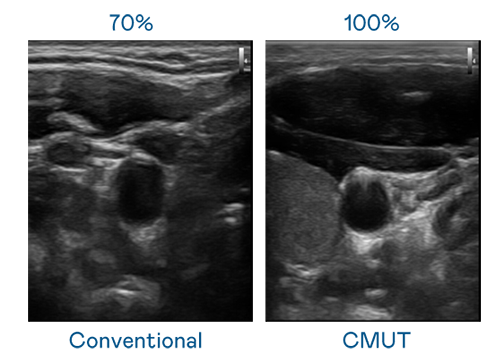

CMUT 技术是一种用电容式微机电元件来产生超音波讯号的技术。与传统 PZT 压电式技术相比,CMUT 频宽增加 30%,更宽频的超音波讯号让影像解析度大幅提升,是实现高影像品质医疗超音波扫描、促进精准医疗发展的关键技术。

大频宽带来超清晰影像

超音波影像的解析度高低,首先取决于探头能发出的讯号频宽。DG视讯 CMUT 可提供高清晰的超音波讯号,提供高频宽、高灵敏度、影像纹理细节更高的超音波影像,协助医护人员缩短影像判读时间及利用精准的医疗影像进行诊断。